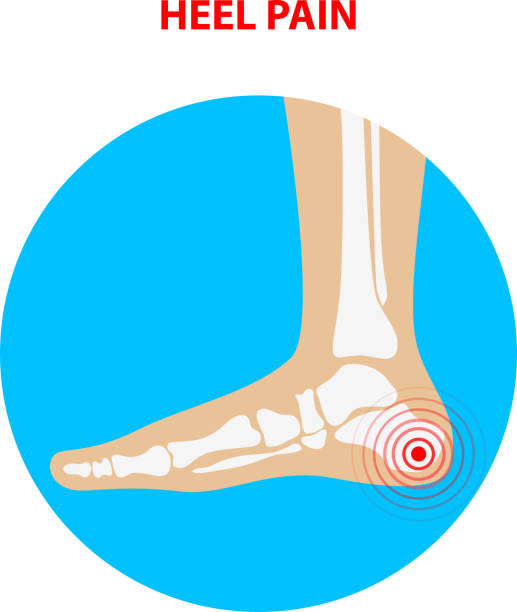

발뒤꿈치가 아픈 이유 1. 족저근막염

발뒤꿈치가 아픈 이유 첫 번째는 족저근막염입니다. 족저근막은 발뒤꿈치 뼈에서 시작하여 발바닥 앞쪽으로 연결되는 두껍고 강한 섬유질 띠입니다. 족저근막은 우리 몸의 중요한 역할을 하는데 아치 모양의 모양새는 우리 몸의 체중을 흡수하기 때문에 걷는 데 중요한 역할을 할 수 있습니다. 족저근막염은 이러한 족저근막에 반복되는 충격으로 근막을 둘러싸고 있는 콜라겐이 변성하면서 염증이 생긴 것을 의미합니다.

이러한 증상은 원래부터 평발이거나 걸음걸이나 생활습관 등으로 발이 변형되며 구조적으로 이상이 생겨서 문제가 생길 수도 있지만 기본적으로 하체 사용을 무리하게 하다보면 문제가 생기게 됩니다. 족저근막염 통증은 개인에 따라 다르지만 기본적으로 발뒤꿈치에 통증을 느끼게 되고 특히 아침 기상후 첫 걸음부터 통증이 나기 때문에 조기에 치료를 받는 것이 중요합니다.